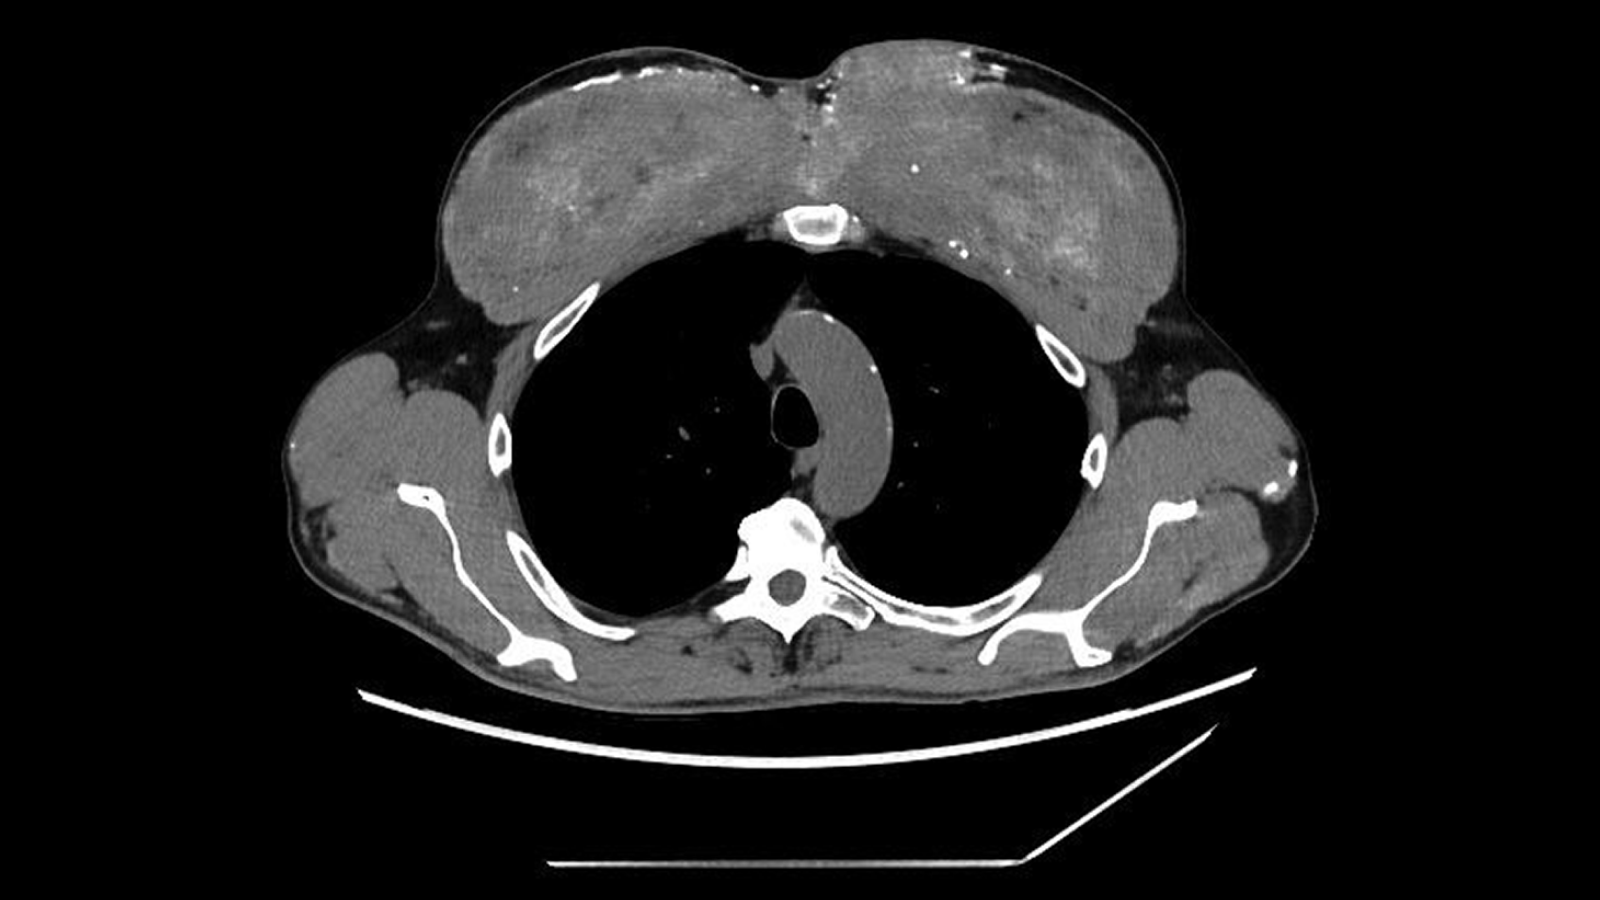

The man was generally stable, but a physical exam showed noticeable changes in his upper-arm and chest muscles, matching the irregularities seen on the scans. The doctors then revisited the patient’s medical history, and he shared a crucial detail: starting about 30 years earlier, he had started receiving “unknown intramuscular injections (probably containing testosterone)” into his chest and upper-arm muscles to enlarge them, according to a report of his case.

The diagnosis: Under the microscope, the muscle was filled with a silicone-like, oil-based substance and surrounded by dense calcium deposits. The team deduced that the man’s past muscular injections probably contained synthol, a substance made primarily of oil that visually “plumps” up muscles, essentially inflating them like water balloons.

In this case, the synthol had triggered a persistent foreign-body reaction — the body essentially responding to material it could not break down. Over time, this reaction produced scarring and calcification, storing large amounts of calcium inside the muscle. And eventually, that calcium made its way into his bloodstream.